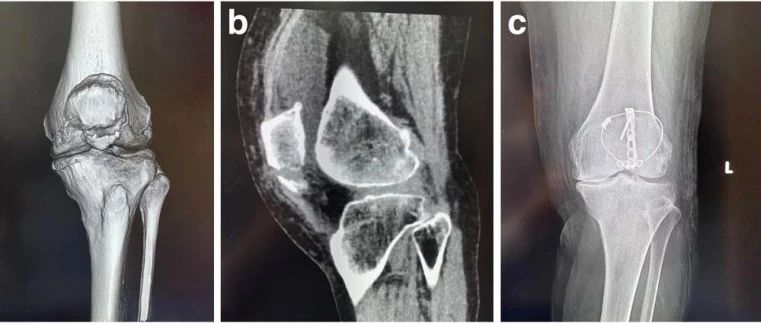

本文未经授权禁止转载髌骨骨折是一种常见的关节内骨折,约占全身骨折的1%。髌骨下极骨折(Inferior pole fracture of the patella, IPFP)是一种发生在髌骨远端1/4,即髌腱附着点的特殊类型髌骨骨折,主要由松质骨构成,无关节面覆盖,不参与髌股关节的组成。IPFP是一种关节外骨折,占髌骨骨折的9.3 ~ 22.4%。造成这种骨折最常见的机制是直接撞击屈曲的膝盖,同时本能地导致股四头肌的强烈收缩。由于其机制,撕脱力和直接打击导致髌极碎片粉碎。...